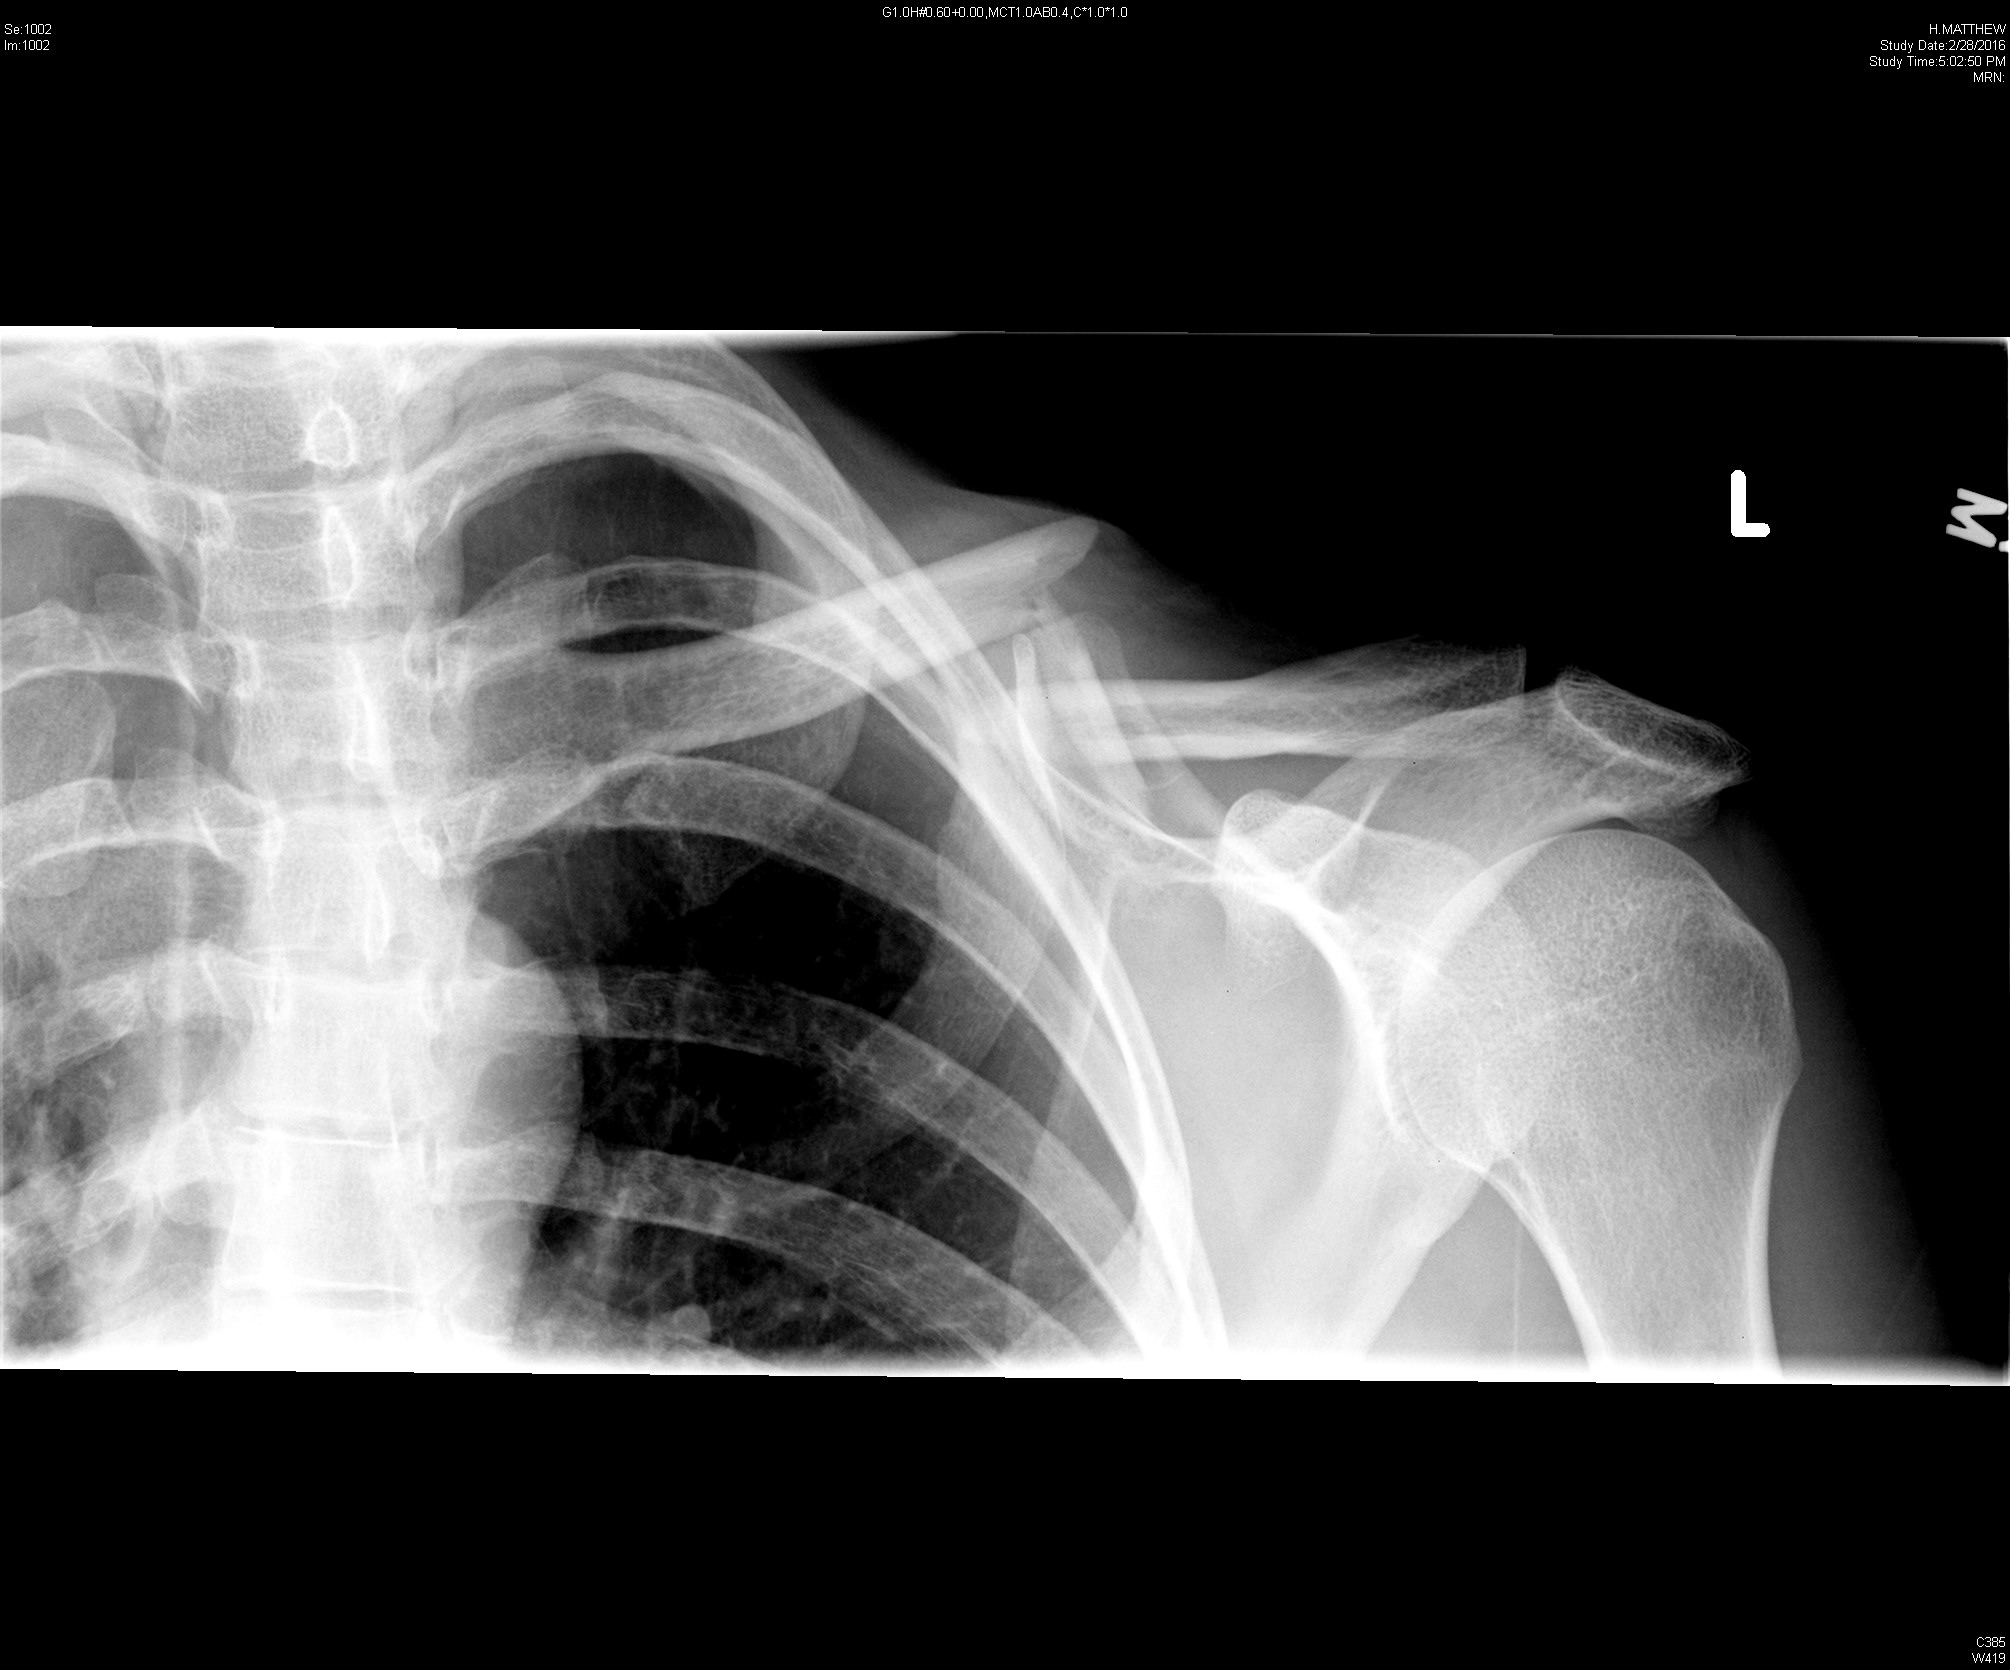

A 23-year-old male presents for a second opinion after a clavicle fracture one week prior. He was tackled in a softball game after hitting a player with a baseball. He had pain and deformity of his left mid-clavicle and initially presented to another hospital where imaging demonstrated a displaced mid-clavicular fracture. He was placed in a sling and referred for outpatient Orthopedic evaluation. He returned to the ED for ongoing pain and was found to have skin tenting (Figure 1). Repeat X-rays (Figure 2) showed “a segmental fracture of the mid left clavicular shaft with inferior displacement by 1.5 shaft widths.”

Figure 2: Clavicle radiograph showing mid-shaft clavicle fracture with displacement